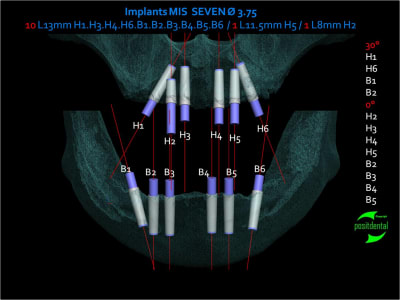

projet implantaire pour février

1er étape le wax-Up, dans ce cas clinique il est réalisé en 3D

Pano de contrôle